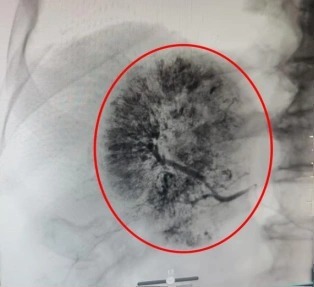

鉴于患者病情危急,传统开腹手术创伤大、风险高,肿瘤微创介入诊疗中心手术团队紧急会诊后,决定为其施行经肝动脉化疗栓塞术(TACE)。术中医生通过股动脉穿刺插入导管鞘,在导丝引导下将导管送至腹主动脉,注入造影剂进行血管造影,清晰显示肿瘤的位置、大小及供血动脉分支。再将微导管选择性插入肿瘤供血动脉,先灌注化疗药物,再注入栓塞剂,精准阻断出血血管,同时切断肿瘤营养供应。术后患者生命体征平稳,腹痛症状明显缓解。复查CT显示,肿瘤出血已完全停止,肿瘤染色消失。

栓塞术前肿瘤染色明显